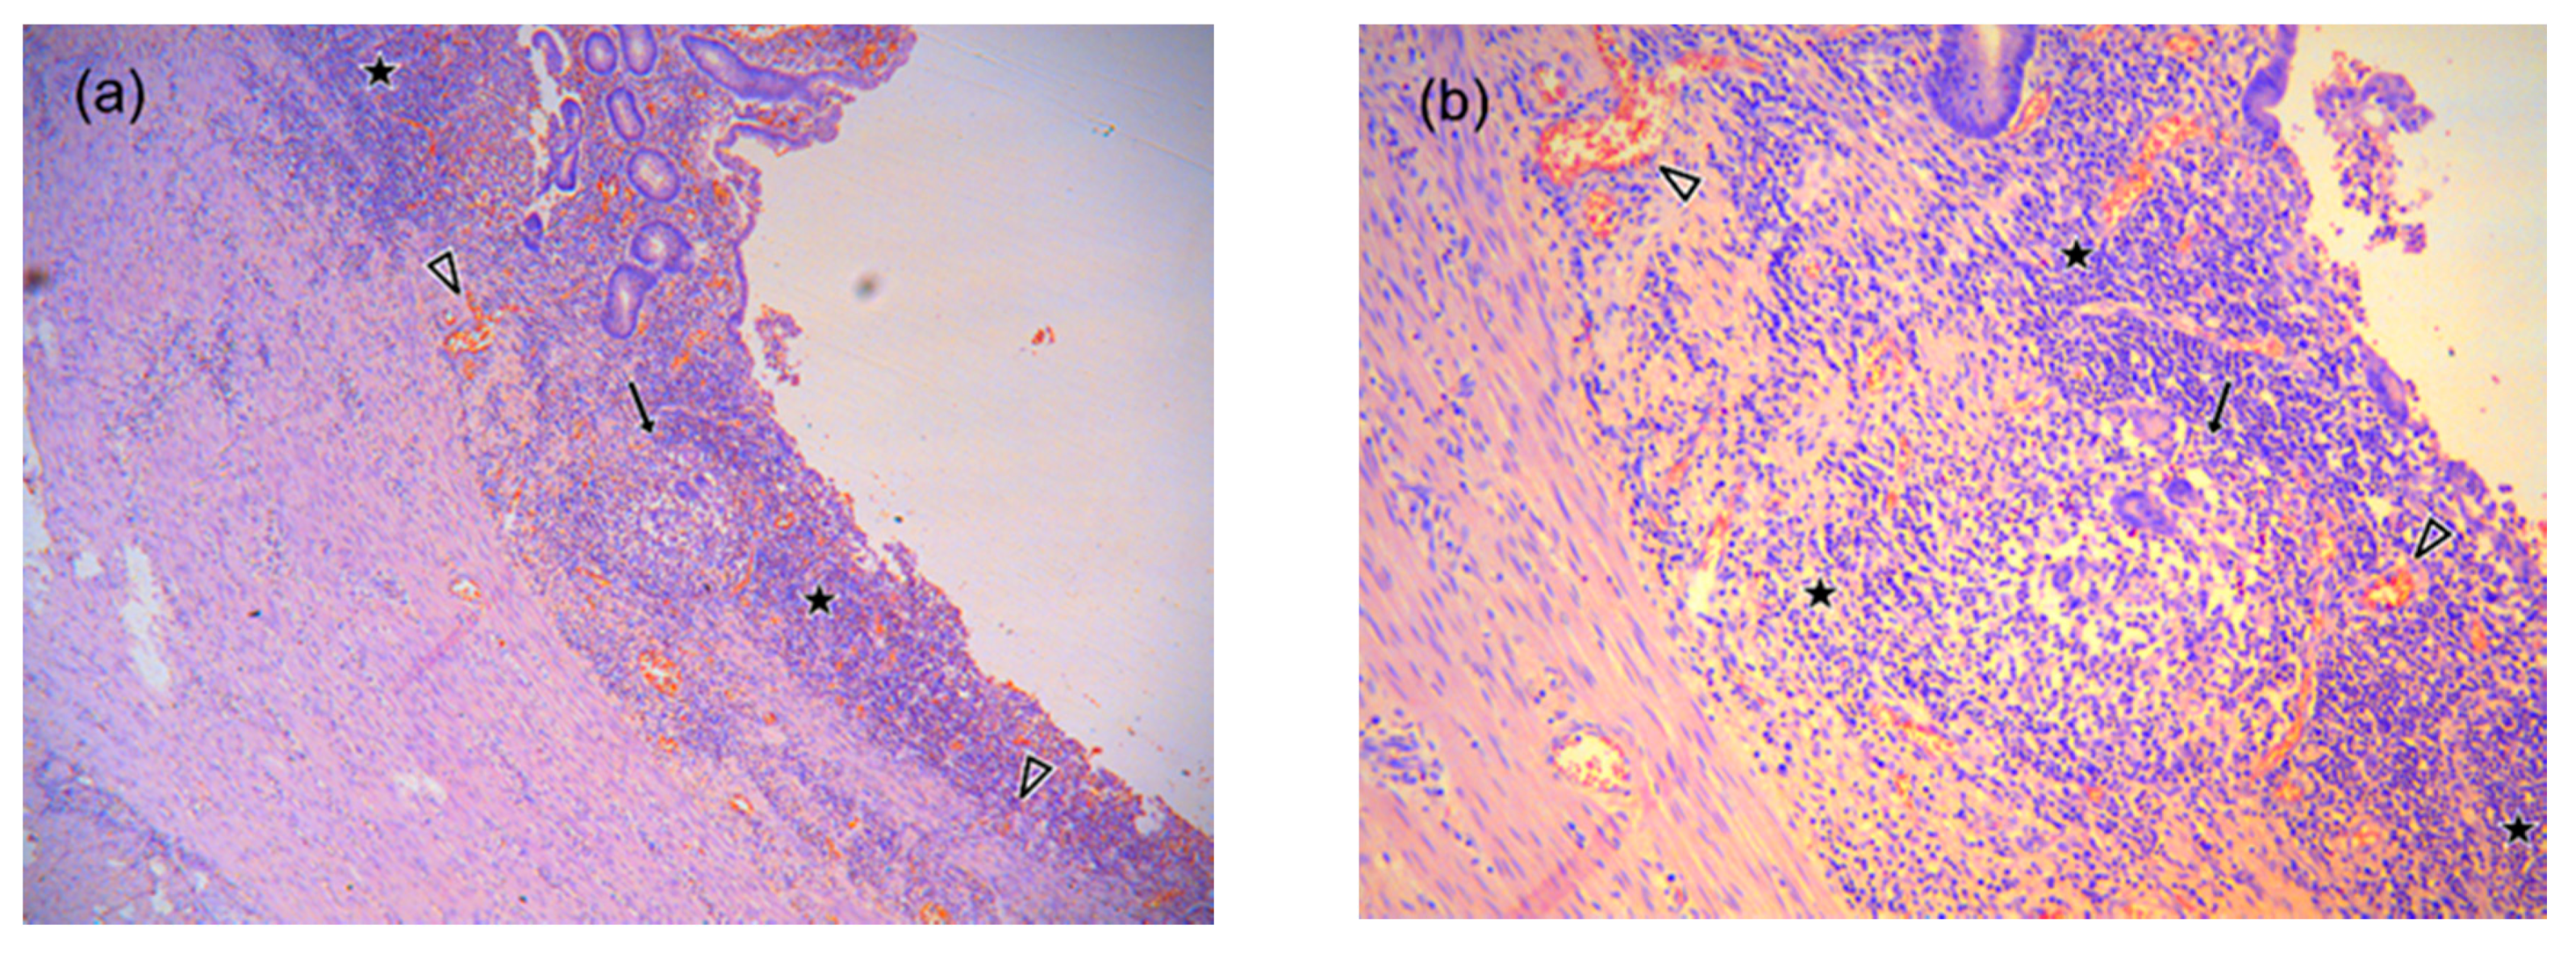

- Geboes, K. Histopathology of Crohn’s Disease and Ulcerative Colitis. In Inflammatory Bowel Diseases; Satsangi, J.S.L., Ed.; Churchill-Livingstone Elsevier: Edinburgh, Scotland; London, UK; Melbourne, Australia, 2003; Volume 18, pp. 255–276. [Google Scholar]

- Feakins, R.M. Inflammatory bowel disease biopsies: Updated British Society of Gastroenterology reporting guidelines. J. Clin. Pathol. 2013, 66, 1005–1026. [Google Scholar] [CrossRef]

- Magro, F.; Langner, C.; Driessen, A.; Ensari, A.; Geboes, K.; Mantzaris, G.J.; Villanacci, V.; Becheanu, G.; Nunes, P.B.; Cathomas, G.; et al. European consensus on the histopathology of inflammatory bowel disease. J. Crohn’s Colitis 2013, 7, 827–851. [Google Scholar] [CrossRef]

- Roger, M.; Feakins, N.A.S. An update on the pathology of chronic inflammatory bowel disease. In Recent Advances in Histopathology 23; Massimo Pignatelli, P.G., Ed.; JP Medical Ltd.: London, UK, 2014; pp. 117–134. ISBN 9781907816857. [Google Scholar]

- Robert Riddell, D.J. Gastrointestinal Pathology and its Clinical Implications, 2nd ed.; Lippincott Williams & Wilkins, Ed.; Wolters Kluwer: Philadelphia, PA, USA, 2014; Volume II, ISBN 9780781722162. [Google Scholar]